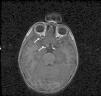

Se interrogó a los padres, que negaron antecedentes familiares de NF1, y se confirmó el diagnóstico tras el hallazgo de al menos 6 «manchas café con leche» de nódulos de Lisch en el iris de ambos ojos, observados por la lámpara de hendidura, y de un glioma del nervio óptico derecho en la resonancia magnética (fig. 1).

Los gliomas de las vías ópticas suelen diagnosticarse antes de los 5 años (75%). Aparecen en el 10-25% de los pacientes, pero solo un tercio son sintomáticos, siendo más frecuentemente quiasmáticos y de bajo grado. Estos niños precisan revisiones oftalmológicas regularmente. Si son asintomáticos se acepta un seguimiento cada 6-12 meses con neuroimagen, siendo la resonancia magnética nuclear la técnica de elección3 (fig. 1).